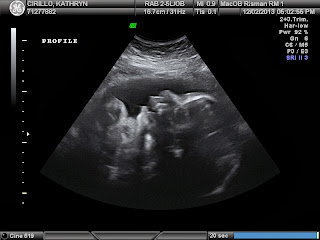

I don't think my words can begin to express how grateful I am for this miracle to be coming into our family in less then 2 months. I cried tears (happy tears) as our sweet ultrasound tech brought these pictures up. She knew how exciting of a time for us this was and she allowed us to enjoy every second. After she left the room and we were waiting for the Dr. to come in, she left the last picture up on the big screen in the room so we could continue to be in awe of it. Cue some more tears at this point, I just can't believe how perfect this little boy is.

Now on to the health stuff... Sam weighs 4.5lbs at 33 weeks. Weight in range= check. Mom's fluid levels being in normal range= check. I was worried about the fluid levels which can be indicative of a concern with my blood pressure if they are too high. Need not to worry about that! Sam's organs measuring properly and in range= check. Then as we are reassured every single ultrasound... his esophagus and stomach are attached = CHECK CHECK CHECK!